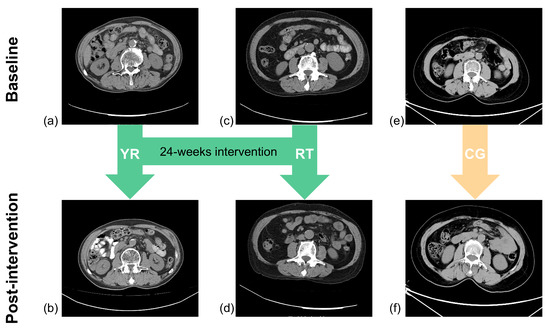

2.2. Study Design

2.2.2. Intervention

- Yi Jin Jing exercise: The training schedule of Yi Jin Jing consisted of two phases of 8 and 16 weeks, respectively. The first phase involved learning the movements: two Yi Jin Jing exercises were practiced in each session. During the second phase, the main goal was to consolidate learning of the exercise, and three Yi Jin Jing exercises were practiced in each session.

- Resistance training: Resistance training consists of a total of five exercises which include two lower body exercises with supine elastic band resistance leg lifts and standing elastic band resistance leg raises, and three upper body exercises, including bicep curls, reverse grip curl, and seated pull down. To maximize strength gains the muscle hypertrophy, the training session was divided into three 8-week periods. The purpose of the first phase was to allow participants to learn and master the training movements using low loads (40.0–60.0% of 1 RM) and high repetitions (12–20) for 2–4 training sets. The second stage aimed to induce muscle hypertrophy and further improve muscle mass and reduce the fat content of the skeletal muscle interstitium by gradually increasing the load with a medium load of (60.0–80.0% of 1 RM), 5–12 repetitions, for 2–4 sets. In the third phase, we used a higher load (70.0–85.0% of 1 RM) and reduced the number of repetitions (5–8 repetitions) for 2–4 sets to further optimize muscle strength and increase maximal muscle power. The RT group underwent 4 sets for each movement, whereas the YR group completed 2 sets, with a 2 to 3 min interval between sets.

- Control group: The CG group underwent conventional treatment, and the nurse educated the participants on sarcopenia and prevention methods, such as increasing protein intake in the diet and participating in more physical activities.